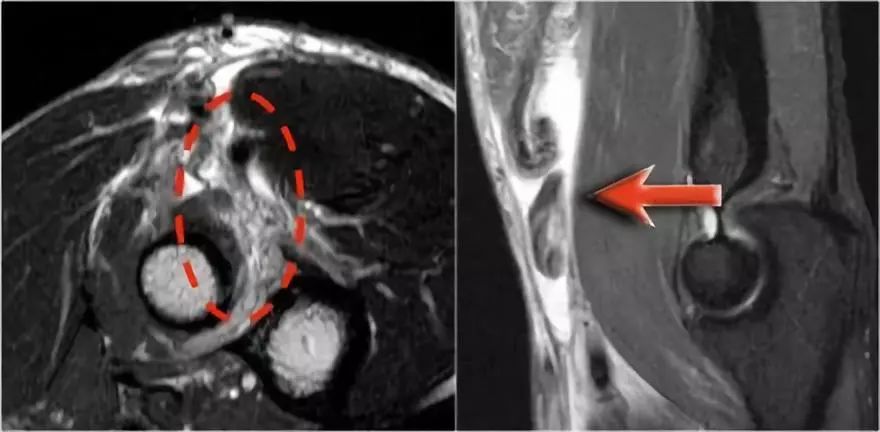

尺神经:在这里,我们看到了肘管内的尺神经。尺骨侧支带的后带形成隧道的底部,而支持带形成屋顶。

该患者有尺神经神经病变。肘管综合征是一种常见的周围神经病变。它产生于肘管内尺神经,其中该神经传递肘管支持带的下方的压缩。

肘管综合征的可能原因● 过度使用● 由于纤维组织中的先天性松弛,尺神经半脱位● 肱骨骨折伴游离体或愈伤组织形成● 由上髁或鹰嘴引起的关节炎● 存在肌肉异常● 软组织肿块:神经节,脂肪瘤,骨软骨瘤,继发于类风湿性关节炎的滑膜炎,感染(例如结核病)和出血。

当他们将尺神经带出隧道时,他们把它放在哪里,它可以是皮下,肌肉下或肌肉内。

因此,当我们回到图像时,您会发现很难找到神经。任何这些皮下结构都可以是转位神经。一种方法是远端跟随结构,直到你发现远端的尺神经位于由脂肪包围的前臂近端的正常位置。然后当你向近端跟随它时,你会发现这是皮下移位。

在这种情况下,有神经炎。神经增大。在T2W图像上有高信号。另一个标志是在矢状图像(箭头)上看到的束的不均匀扩大。

桡神经:在桡骨头水平可以最好地识别桡神经,在那里你可以看到桡骨隧道中的浅表和深支(箭头)。这是寻找桡神经的非常一致的地方。

深分支形成后骨间神经,穿过Frohse拱门(箭头)的旋后肌。